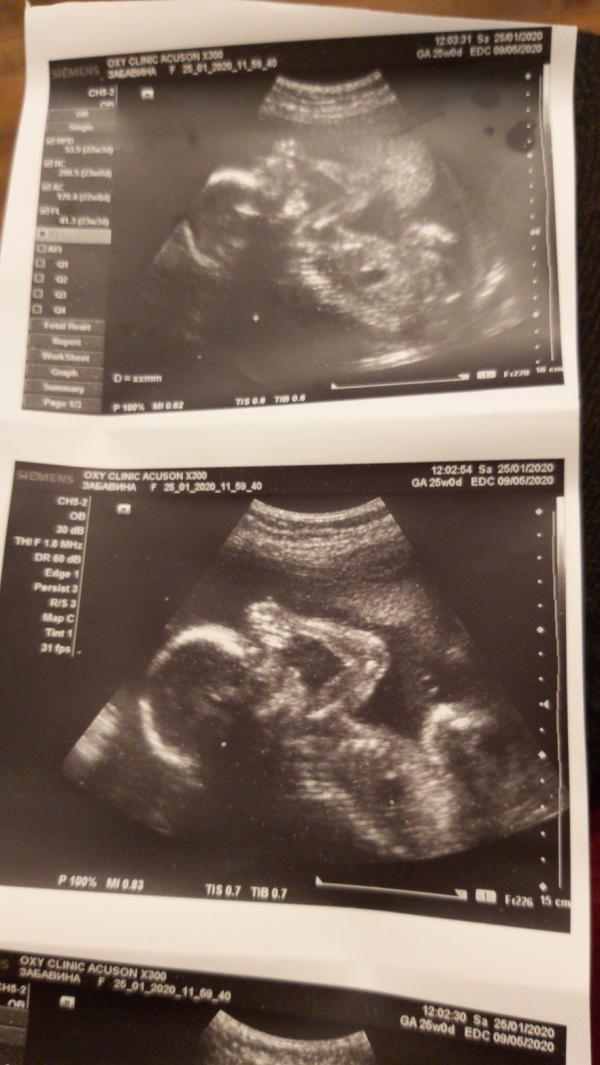

Наш малыш🤰👶

Супер так хорошо видно) у нас очень активный ребёнок и поэтому фото непонятные)))